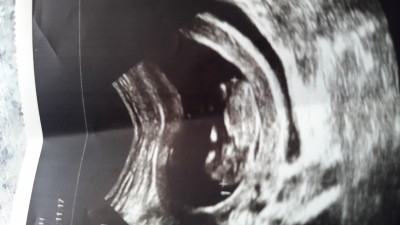

14 haftalığız tecrübeli anneler cinsiyet tahmini yapabilir mi

Bana da kız gibi geldi

Kiz diyorum canim. Kese şekline göre yorumladim sadece.

Cinsiyetini merak etmiştiniz bugün öğrendim net değil ama kıza benziyor dedi doktor

Erkek bebek bnce kesesi fasulye gibi. Allahım gönlünden ne geçiyorsa hayırlısıyla onu nasip etsin

Bacak arası açık duruyor erkek gibi canım

Bacak arasında çıkıntı var erkek sankı

kiz olsub